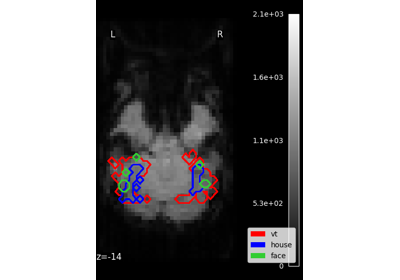

Plot Haxby masks